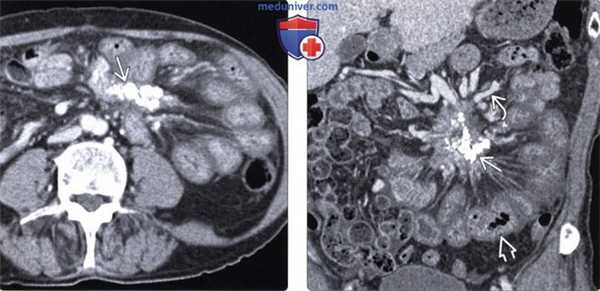

(Слева) На аксиальной КТ с контрастным усилением визуализируется кальцинированное объемное образование в левом верхнем квадранте брыжейки, стягивающее петли кишечника.

(Справа) На корональной КТ с контрастом у этого же пациента определяется обызвествленное объемное образование. Обратите внимание на венозные коллатерали, сформировавшиеся в результате обструкции верхней брыжеечной вены, а также диффузное утолщение стенки тонкой кишки из-за обструкции венозных/лимфатических сосудов. В данном случае изменения обусловлены гистологически подтвержденным стягивающим мезентеритом.